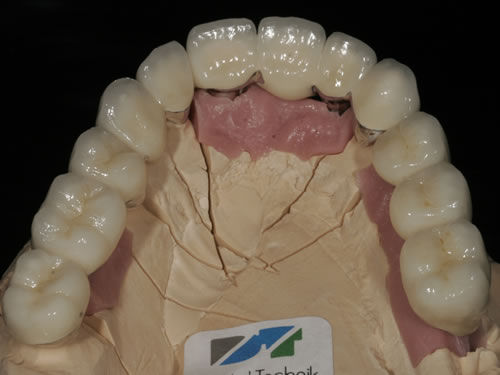

Die Arbeiten, die der Zahntechniker anfertigt, sind sehr unterschiedlich und zum Teil äußerst kompliziert. Sie richten sich danach, in welchen Bereichen die Implantate eingesetzt wurden und welche Aufgaben sie übernehmen sollen. Häufig erfolgen von der Abformung der Implantate noch einige Sitzungen, die Gerüstanproben, Kieferrelationsbestimmungen, Kosmetikanproben etc. umfassen, ehe der neue Zahnersatz endgültig eingesetzt und auf Funktion getestet werden kann.

Für den zahnlosen Ober- und Unterkiefer werden dies häufiger Stegkonstruktionen oder Teleskopversorgungen sein (Abb. 8.8 bis 8.16).